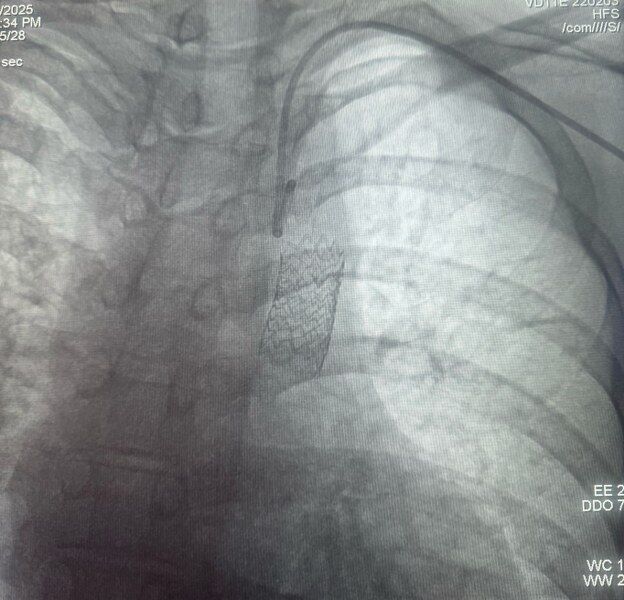

Kardiyoloji ve Kalp Damar Cerrahisi uzmanları Prof. Dr. Ahmet Karagöz, Prof. Dr. Osman Can Yontar ve Dr. Öğr. Üyesi Emrah Ereren’in ortak çalışmasıyla, hastaya cerrahi kesi yapılmadan kasık damarından girilerek greft stent yerleştirildi. Kardiyolojide nadiren uygulanan bu yöntemle daralan bölge başarılı bir şekilde açıldı. İşlem sonrası hasta sağlıklı bir şekilde taburcu edildi.

Aort koarktasyonu tedavisinde ilaç tedavisi, balon anjiyoplasti, stent yerleştirme ve cerrahi müdahale gibi seçenekler bulunuyor. Samsun’da uygulanan stent yöntemi, minimal invaziv olması nedeniyle hastaya hem konfor hem de hızlı iyileşme sağladı. Ancak uzmanlar, bu hastaların ömür boyu düzenli takip altında olması gerektiğini hatırlatıyor.